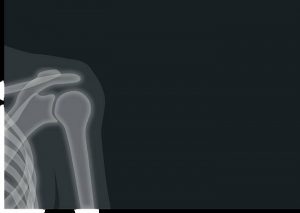

Плечо человекаАртроз плечевого сустава — это дегенеративное заболевание, характеризующееся повреждением хрящевой ткани и изменениями в структуре сустава. Несколько факторов могут способствовать развитию артроза плечевого сустава.